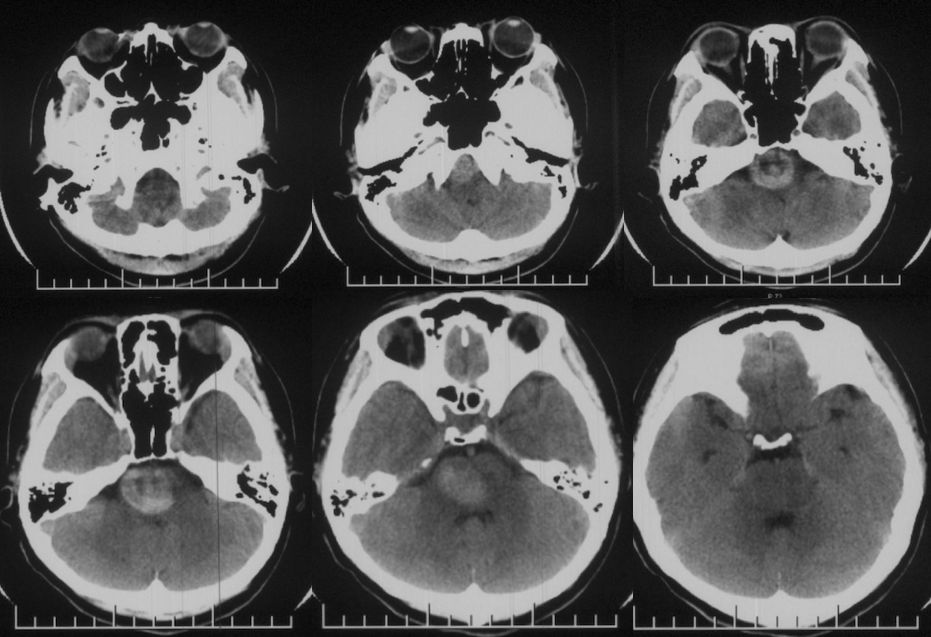

术前影像学检查

当地医院头CT:右侧脑干占位(2019-09-06)(图1)。

图1